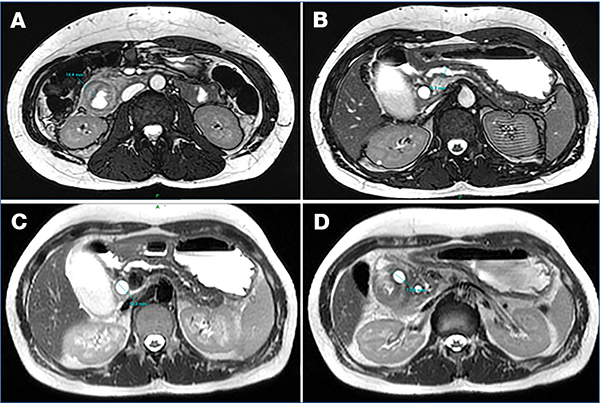

MRI-vizsgálat csupán egy esetben állt rendelkezésre (4. ábra), amely során a pancreas 10–13 mm vastagságúnak imponált, a Wirsung-vezeték teljes hosszában tágult, a duodenum falának megvastagodása pedig szintén megfigyelhető volt. Vizsgálataink során az ultrahang (UH) és a komputertomográfia (CT) bizonyultak a leginformatívabb képalkotó eljárásoknak (1. táblázat); ezek szolgáltatták a legtöbb releváns morfológiai információt a diagnosztikai döntéshozatalhoz (5. és 6. ábra).

(A) A duodenum leszálló szárán egyenetlen falmegvastagodás figyelhető meg (14,4 mm); (B) A Wirsung-vezeték a fej-test határon 6,7 mm, kaliberingadozással végig tág; (C) Tágult ductus choledochus (13 mm); (D) Cystosus 13,9 mm átmérőjű képlet a pancreas medialis falán, amely a duodenum felé boltosul